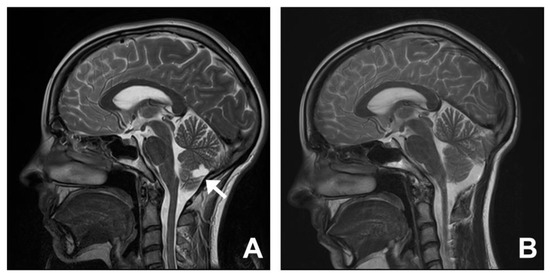

3.5. Group Five. Cysts: Arachnoid, Choroid Plexus, and Cerebellum

| 13 | 57 | M | Headache Visual changes | 1 | Arachnoid cyst | Surgical decompression and fenestration of cyst | Improved |

| 14 | 23 | F | Headache | 5 | Extra-axial cyst | Surgical decompression and excision of cyst | Improved |

| 15 | 61 | F | Headache | 1 | Supra-cerebellar cyst | Expectant management | Improved |